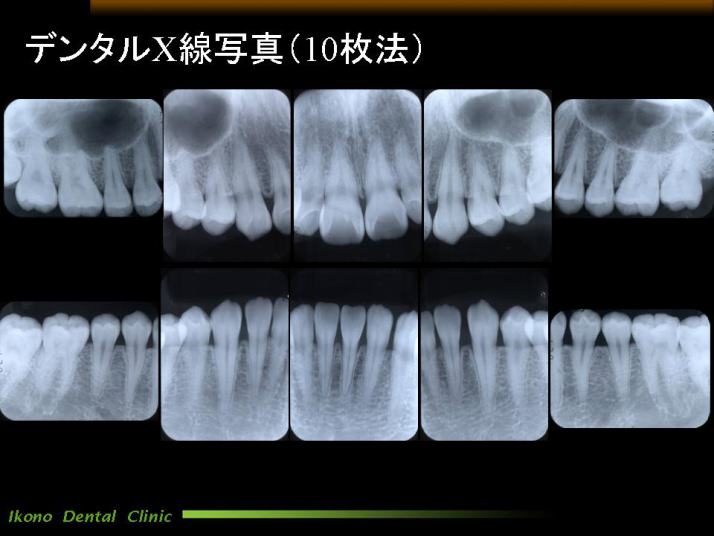

デンタルX線写真

お口全体の虫歯や歯周病の検査のために当医院ではパノラマX線写真や10枚法という方法を使っています。

10枚法は細かいところの歯の異常等を発見するのに最も適しています。 歯科用のレントゲンによる10枚法の撮影被爆量は安全基準をはるかに下まわっておりますのでご安心ください。